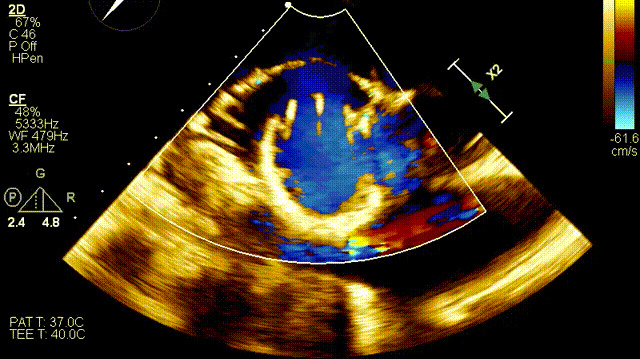

術后超聲

手術在全麻狀態(tài)下開展,此次手術采用經右側頸靜脈入路的方式將輸送器送入患者心臟內,在TEE及DSA引導下調整輸送器頭端角度,使得輸送器與三尖瓣瓣環(huán)平面垂直。在輸送器進入右心室后釋放室間隔錨定裝置,而后釋放瓣葉夾持件(2個耳片結構)成垂直狀態(tài)。在TEE及DSA確定夾持件固定至三尖瓣葉根部且位于右室側后釋放人工瓣心房側盤片。隨后調整瓣膜同軸性以及室間隔錨定件位置(貼合室間隔),前推藏針管并固定,進而釋放室間隔錨定裝置,并再次確認瓣膜位置、穩(wěn)定性及同軸性,合攏輸送鞘后撤出輸送器,完成LuX-Valve Plus人工三尖瓣瓣膜的植入。